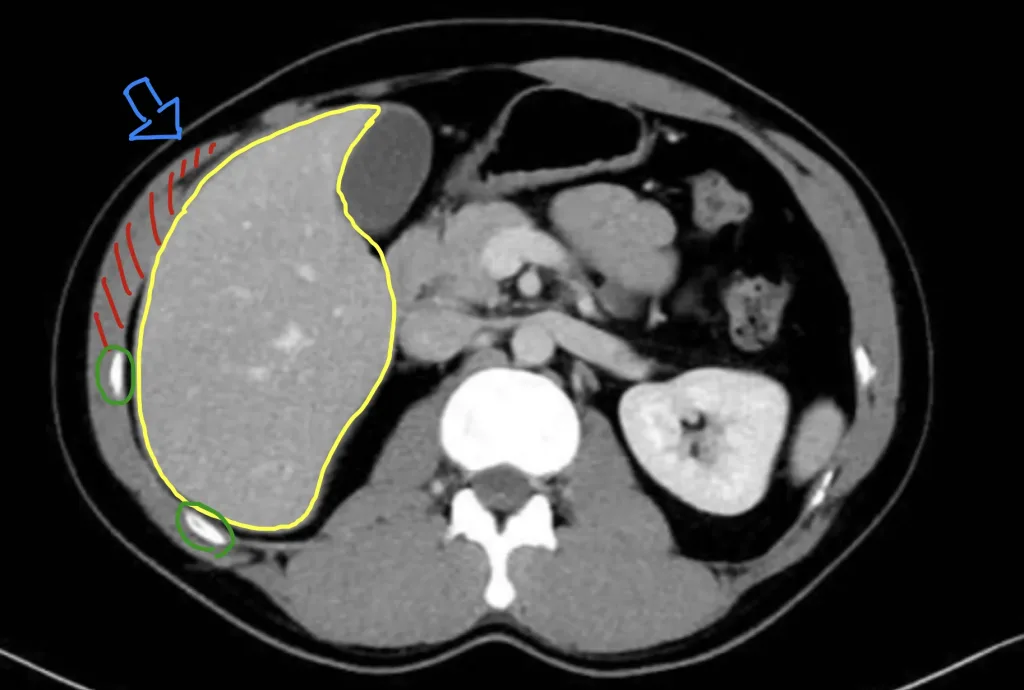

この図は肝臓の下の方のCT画像です。黄色の線で囲われている部分が肝臓の下部です。赤色の斜線が筋肉(今回は外腹斜筋、内腹斜筋、腹横筋が含まれます)で、緑で囲われている白く光っているものが肋骨です。この図から分かるように、この位置では肝臓は肋骨に守られておらず、薄い筋肉があるのみです。また筋肉も付着部に近く、鍛えても十分に太くはなりません(どんなに鍛えても力こぶの肘の付け根が太くならないイメージ)。よってボディブローのような青矢印の力に対しては、筋力トレーニングでは対応できないことになります。